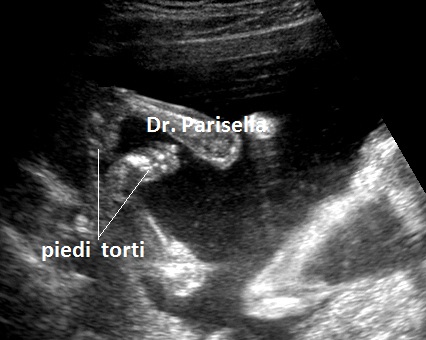

E' una malattia genetica rara caratterizzata da nanismo, palatoschisi e facies peculiare.  Il nanismo è dovuto ad ipoplasia ed incurvamento bilaterale e simmetrico del femore; il femore può essere ipoplasico o assente. La facies è caratteristica: naso corto, radice del naso allargata, micrognatia, palatoschisi, labbro superiore sottile, orecchie allungate ed inclinate posteriormente. Si osserva anche piede torto.

La diagnosi ecografica si basa su:

5) piede torto